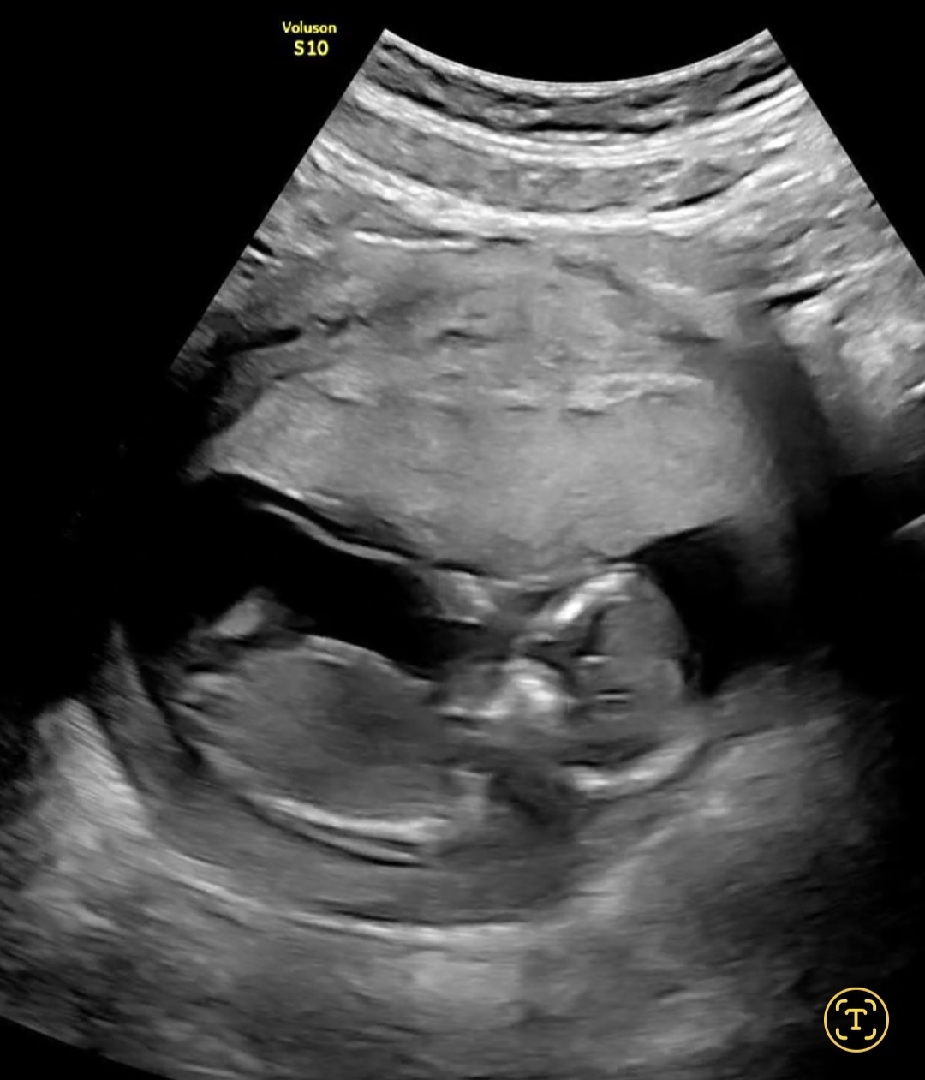

12주 5일 각도법 한번씩 봐주세요!

한번씩 봐주시고 투표 부탁드릴게요!